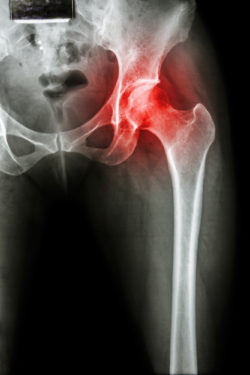

hip implant complications DePuy Zimmer Stryker xrayA woman has filed a Zimmer Durom cup lawsuit against the makers of the metal hip implant system after she suffered severe personal injuries as the result of its use.

Virginia was implanted with the Zimmer Durom cup when she underwent a total hip replacement on June 15, 2015. According to the Zimmer Durom cup lawsuit, Virginia’s wounds healed without any complications, and her x-rays showed that the device was in the proper place.

The doctor stated that he saw that the Durom Cup was failing based on x-ray images indicating “it was separating or loosening from the bone, causing the metal cup to move around in the hip socket and rub against the bone rather than fusing to the bone, causing patients crippling pain.”